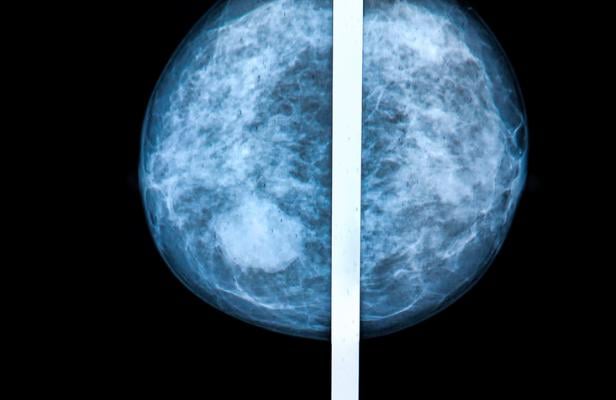

March 30, 2022 — Breast density notifications aim to educate women about the risks of high breast density, defined as having more fibroglandular tissue than fatty tissue, as visualized on a mammogram. Prompted by activists whose own breast density had obscured breast cancers on their mammograms, 38 U.S. states and Washington, DC, have enacted legislation requiring written notification of a patient’s breast density (DBN) after a mammogram and language for a federal notification is forthcoming from the U.S.A. Food and Drug Administration.

Yet, these notifications were developed with limited input and without extensive testing among women in the general population, and many are written at a high literacy level, often discordant with population literacy levels. Now a new study from Boston University School of Medicine (BUSM) has found women had varying preferences for learning about personal breast density, only partly associated with literacy level or race/ethnicity.